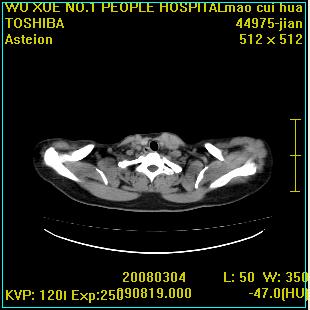

标题: CT12025:男,50岁,左肩活动受限半年。 [打印本页]

标题: CT12025:男,50岁,左肩活动受限半年。

肩关节骨质破坏呈小囊状,其周软组织轻度肿胀,余未见异常。

考虑:肩袖损伤。建议mri。

左侧肱骨头密度不均匀,高低混杂,周围软组织略肿胀,考虑结核性病变。

左侧肱骨头密度不均匀,高低混杂,髓腔密度稍高,周围软组织略肿胀,肌间隙模糊,考虑慢性骨髓炎可能。密切结合临床!

肩关节周围软组织轻度肿胀,肌间隙模糊,余未见异常。

考虑:肩周炎。